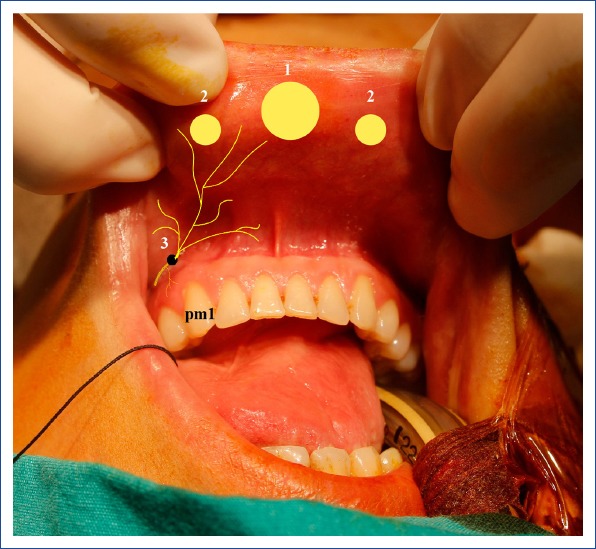

Figure 7.

Port site incisions for a transoral endoscopic parathyroidectomy vestibular approach.

1: A 10-mm midvestibular camera port incision site; 2: A 5-mm working port incision site on the lateral side; 3: Mental foramen, source of the mental nerve; pm1: First premolar tooth.

Transoral parathyroidectomy: A transoral parathyroidectomy has been included in the classification of Natural Orifice Transluminal Endoscopic Surgery (NOTES), and was first performed through the base of the mouth.[72] However, this pathway was not often used, and it was eventually abandoned due to severe tissue damage, a high complication rate, a high rate of conversion to open surgery, and limited technical mobility during surgery. In recent years. Anuwong[73] described a transoral endoscopic thyroidectomy (TOETVA) with a vestibular approach and reported that it is a safe method that can be performed with minimal complications.

A 10-mm camera port was used with a 2-cm incision made from the superior of the inferior frenulum from the midline, and two 5-mm working ports at the lateral junction between the canine and first premolar teeth were inserted in the oral vestibular area with 6 mmHg CO2 insufflation pressure. Subsequently, parathyroidectomy (TOEPVA) was performed with this technique, and a transoral vestibular robotic parathyroidectomy was introduced.[74–76] (Fig. 7). Although use of TOETVA is becoming more widespread in the world, the number of TOEPVA cases is still limited. While this method does not leave visible scars on the neck, it requires greater exposure of the subplatysmal area and more tissue dissection than a lateral open MIP. This appears to be a feature preventing widespread use.